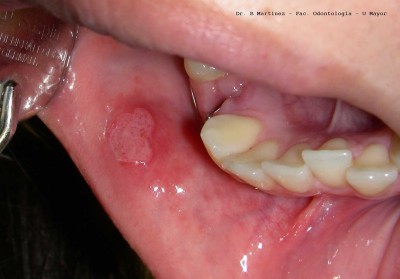

La hiperplasia se caracteriza por un agrandamiento difuso y relativamente avascular nodular o liso de las encías, que también puede cubrir los dientes. El tejido hipertrofiado a menudo debe extirparse. Si es posible, deben sustituirse los fármacos causantes. Una higiene bucal...